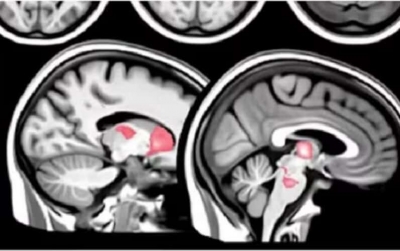

EU-SEARCH NOVICE | Velika študija opozarja: Pri cepljenih proti Covidu obstaja dolgoročno tveganje za poškodbe možganov ...

Velika študija opozarja: Pri cepljenih proti Covidu obstaja dolgoročno tveganje za poškodbe možganov (28.04.2025) | newsexchange ... Skupina vodilnih italijanskih znanstvenikov je izdala zaskrbljujoče opozorilo o katastrofalnih dolgoročnih zdravstvenih tveganjih za ljudi, ki so prejeli mRNA "cepiva" proti covidu.Raziskovalci, ... | Podobno